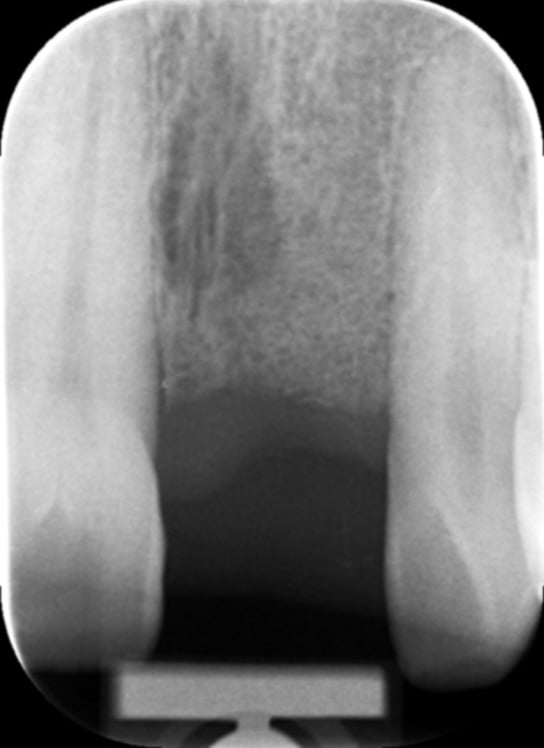

Gallery - Dental Implants

Case 2

Before After